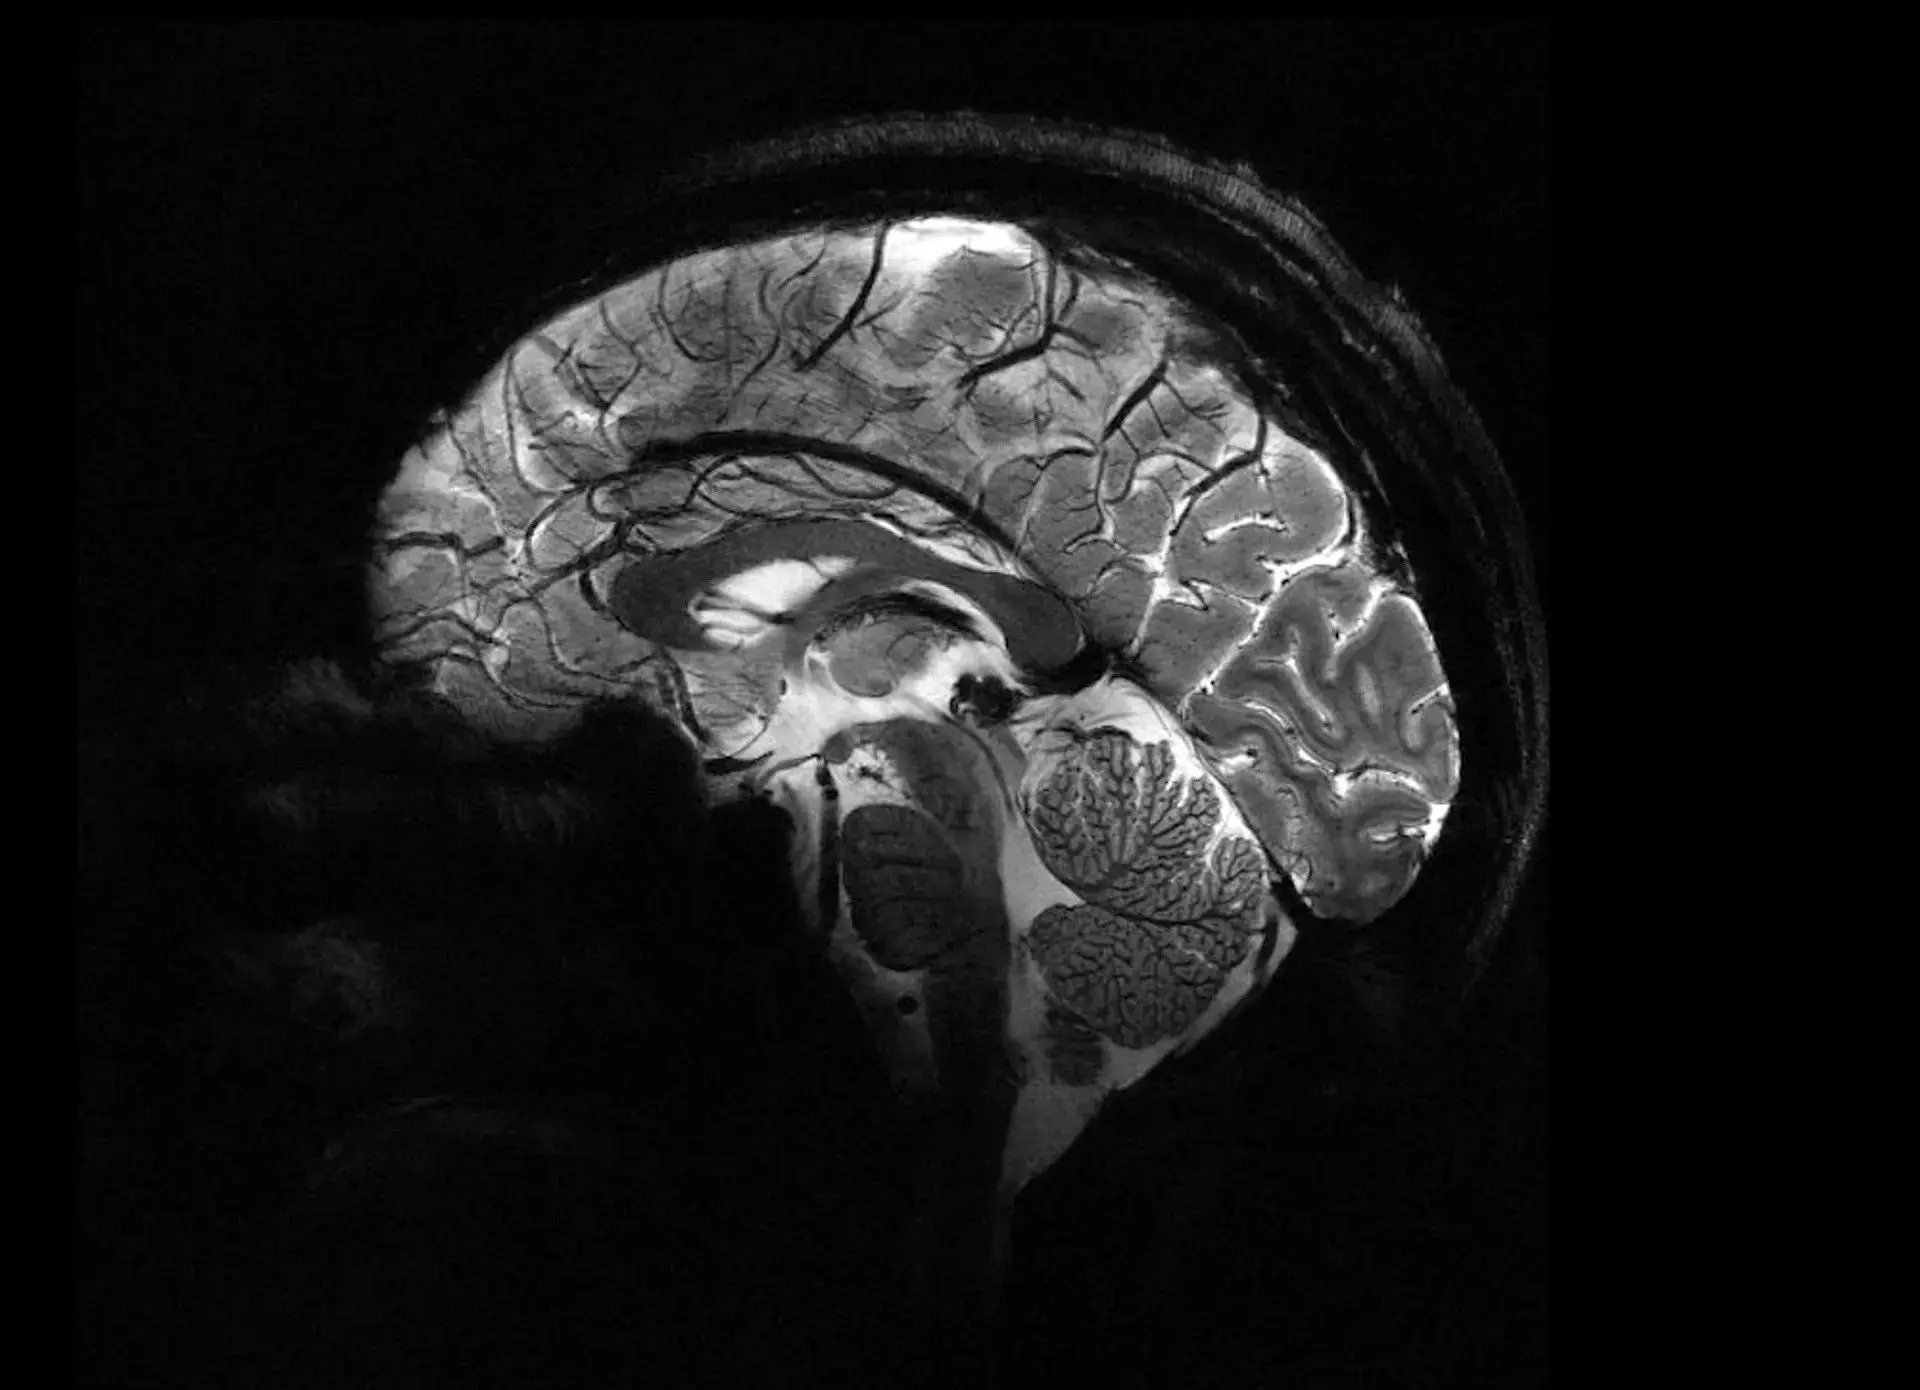

به نوشته نیواطلس، تصاویری که توسط این دستگاه - موسوم به «ایزولت» (Iseult) - از مغز انسان به ثبت رسیده دارای وضوح و کیفیت فوقالعاده بالایی است که دانشمندان را قادر میسازد فرآیندهای ذهنی را بهتر درک کنند و به درمان بیماریهای عصبی بپردازند.

قدرت بیشتر دستگاه یادشده، مزیت اصلیِ آن است که باعث میشود تصاویر مغز با وضوح بسیار بالاتری همراه شود و فرآیند عکسبرداری نیز سریعتر به پایان برسد. ایزولت میتواند تنها طی 4 دقیقه، تصاویر دقیقی از بافت مغز به اندازه 0/2 میلیمتر را ارائه دهد. این ویژگی به پزشکان اجازه میدهد تصاویر دقیق از هزاران سلول مغزی را به شکل همزمان و در کوتاهترین مدت در اختیار داشته باشند.